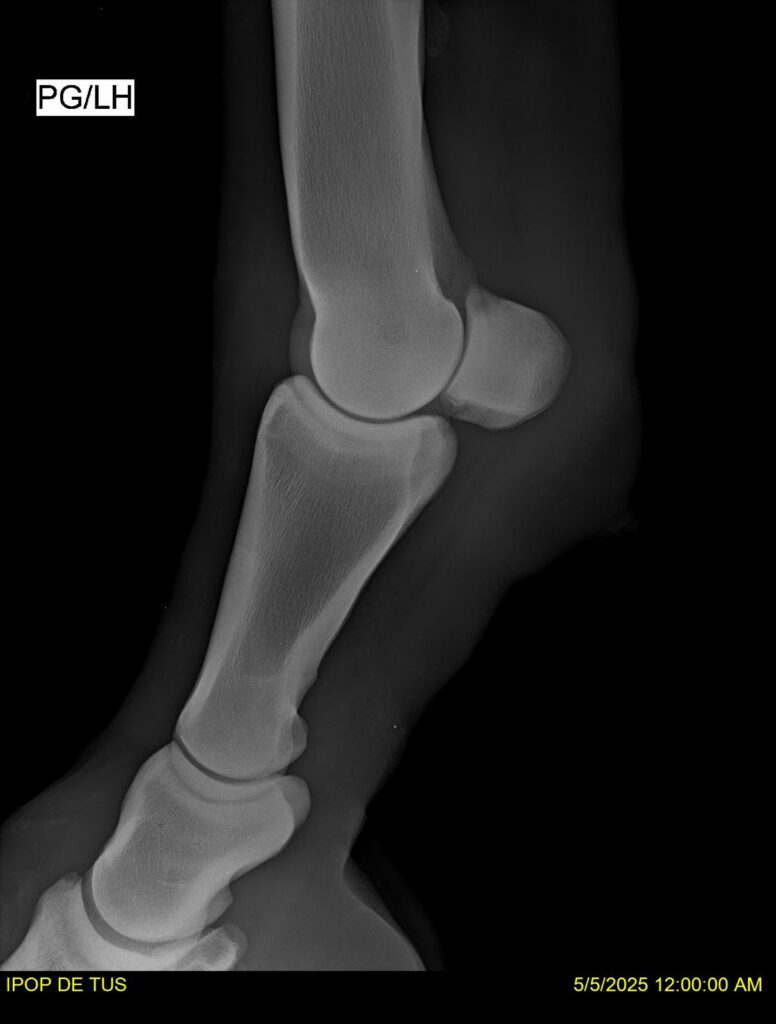

IPOP DE TUS, selle français, hongre, prendra 8 ans en 2026. LIFESTYLE x EROTICBLUS MONTOIS. Sans faute sur 125 et 130. Gentil cheval, respectueux avec des moyens et de la force. Transport OK, maréchalerie OK (pieds nus), santé RAS, Bilan clichés radios + clinique OK.

RADIOS ET CLINIQUE